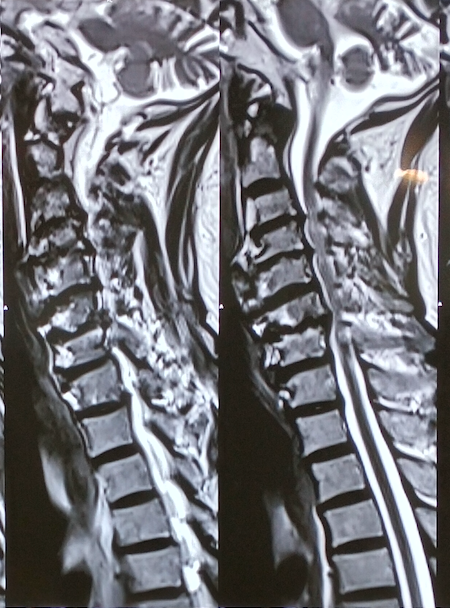

- MRI Cervical Spine: Gold standard to identify spinal cord compression and signal changes